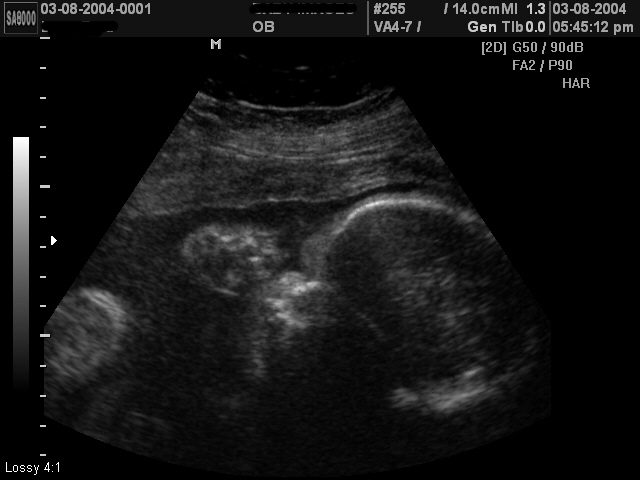

Below are some ultrasound images of a baby girl whose parents were told to expect a boy. Click to enlarge.

28 week girl ultrasound, gender was wrong28 week girl ultrasound, thought to be boy28 week girl ultrasound, technician said boy28 week girl ultrasound, gender said to be boy28 week girl ultrasound, not boy as predicted